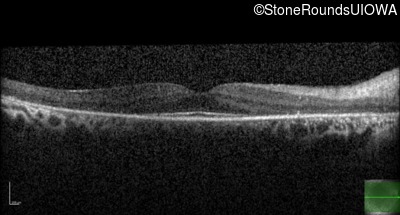

Optical Coherence Tomography - Right - 20/30 -1

Exemplar / OCT Stack